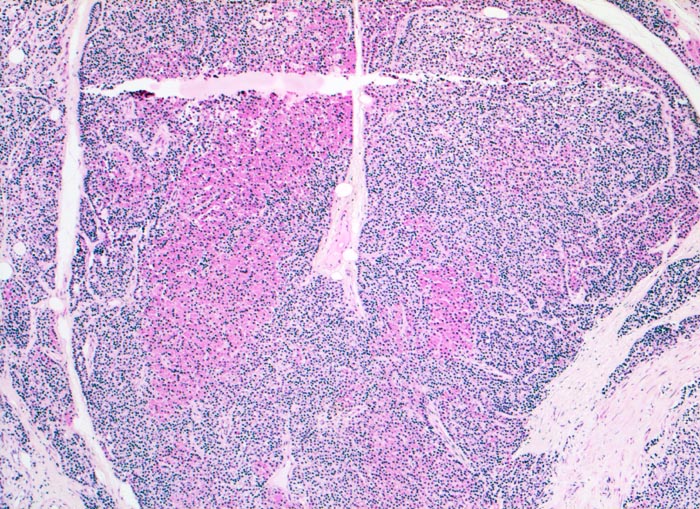

noduläre Nebenschilddrüsenhyperplasie

Knotiges Parenchym ohne Fettzellen. Die Knoten sind durch Septen voneinander abgegrenzt. Die Knoten bestehen aus Hauptzellen und onkozytären (roten) Zellen.

Der Patient leidet an einer chronischen Niereninsuffizienz. Die glomeruläre Filtrationsrate ist auf 25% reduziert. Unter anderem ist eine Hypokalzämie und eine Hyperphosphatämie vorhanden. Die Serumkonzentration des Parathormons ist erhöht. Die Diagnose eines sekundären Hyperparathyreoidismus wird gestellt.